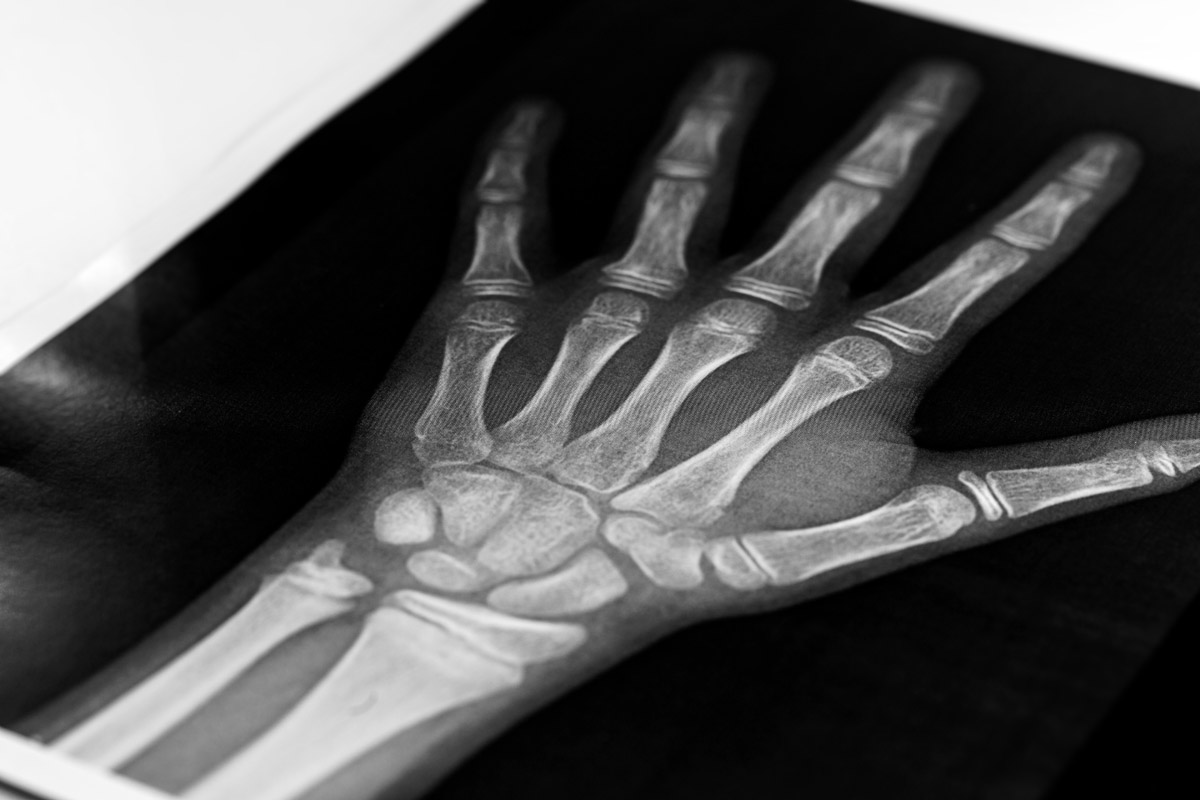

Как выглядит трещина в кости

При патологическом состоянии на рентгеновском снимке заметен небольшой линейный дефект или мелкая щель. Нарушение целостности появляются в результате травмы, стрессового фактора, физиологических процессов старения организма.

Постановка окончательного диагноза происходит при помощи рентгенографии. Рентгенограмма хорошо визуализирует линию разлома. В ряде случаев проводится компьютерная томография. КТ способствует более точной оценке текущего состояния проблемной зоны.

Рентгенография дает возможность увидеть костную мозоль в проблемном участке. Недостатком является то, что мозоль формируется спустя 2,5-3 недели после повреждения. Новые технологии (КТ, МРТ) способствуют визуализации свежей травмы.

Окончательный диагноз устанавливается на основании результатов осмотра, диагностики (рентгенографии, КТ, МРТ).